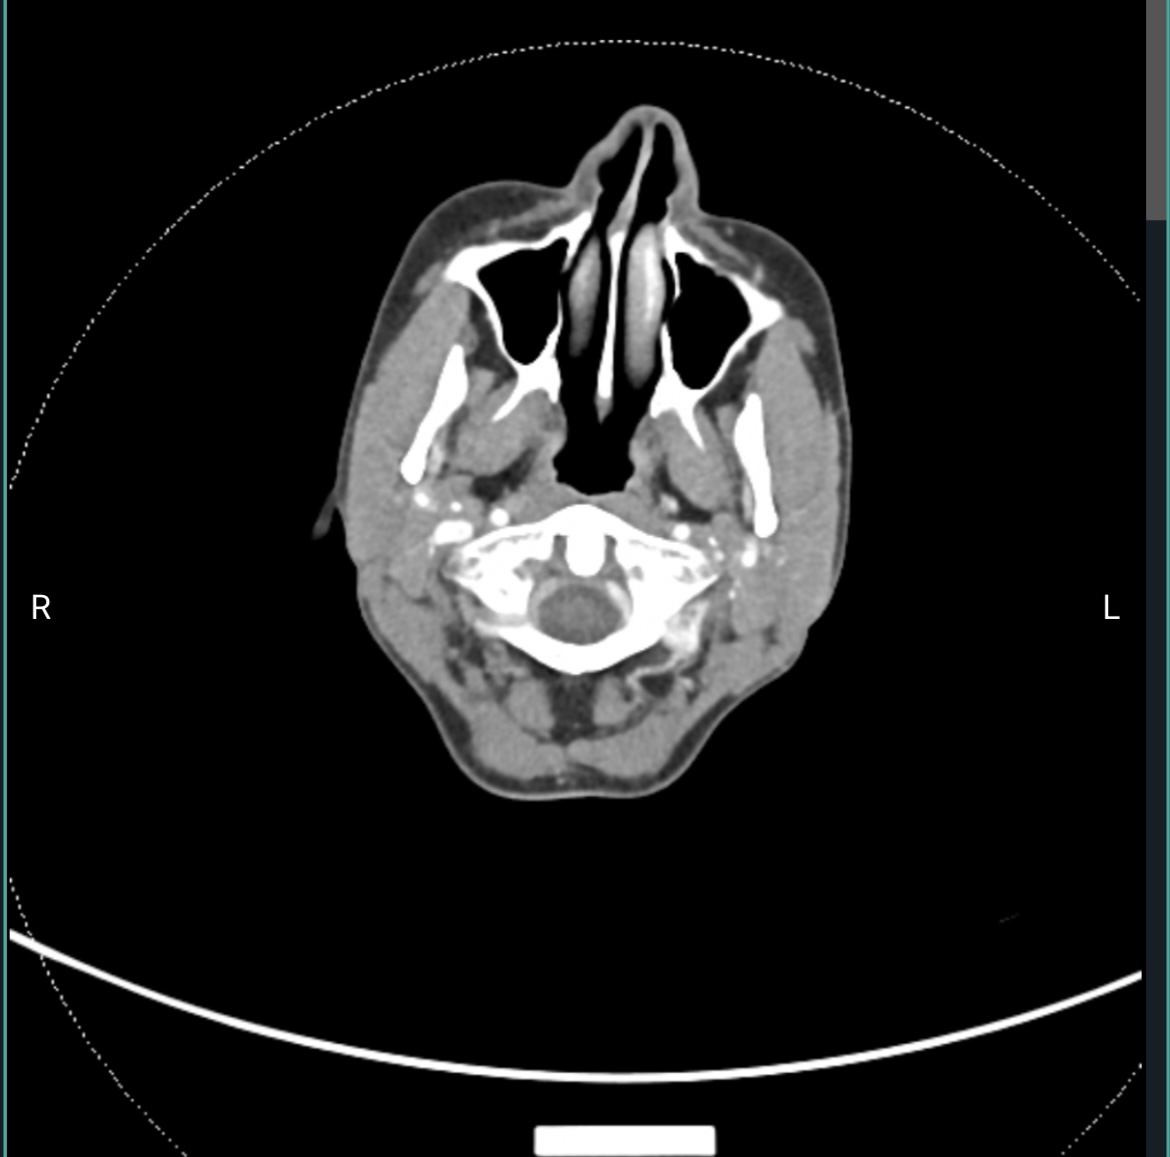

@Coco1 are you able to show me the axial view at the level of C1? I can check if your IJVs are getting compressed between your styloids and C1. I’ve attached my own imaging to help you locate C1. It’s the top vertebrae with wings and a white circle in the top middle!

Your left styloid is really close to your C1. This poses a potential issue for your left IJV and left vagus nerve, since typically, the IJV and vagus nerve are between the styloid and C1. However, I don’t see your IJV there. Maybe this is because it doesn’t have contrast in it, or it’s because it’s further out to the side (where I labelled “left IJV?”). Nonetheless, the styloid should not be that snug against C1 because it risks irritating and/or compressing nerves.

On your right side, the styloid seems to be an o.k distance from your IJV. The IJV may have some compression against C1, but not sure if this is enough to cause problems.

I’m just noticing this as I write this, but the white glow in the bottom right of the image that hugs along the bottom of the C1 transverse process appears it could be a collateral vein. We typically develop these in response to IJV compression, so the blood can flow out of the brain. The fact that this is on the same side (i.e., your left side) as the styloid that is abnormally close to your C1, I suspect your left IJV is being compressed.